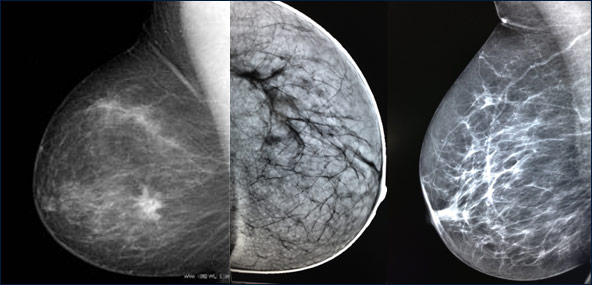

- 1) mammografie 2D e 3D

- 2) le ecografie ad alta definizione

Viene offerta pertanto la possibilita’ di una diagnosi completa grazie ad un percorso

“integrato”,spesso in una unica seduta,con risparmio di tempi e di costi.grazie anche

all’ausilio di apparecchiature di ultima generazione e di recentissima acquisizione.